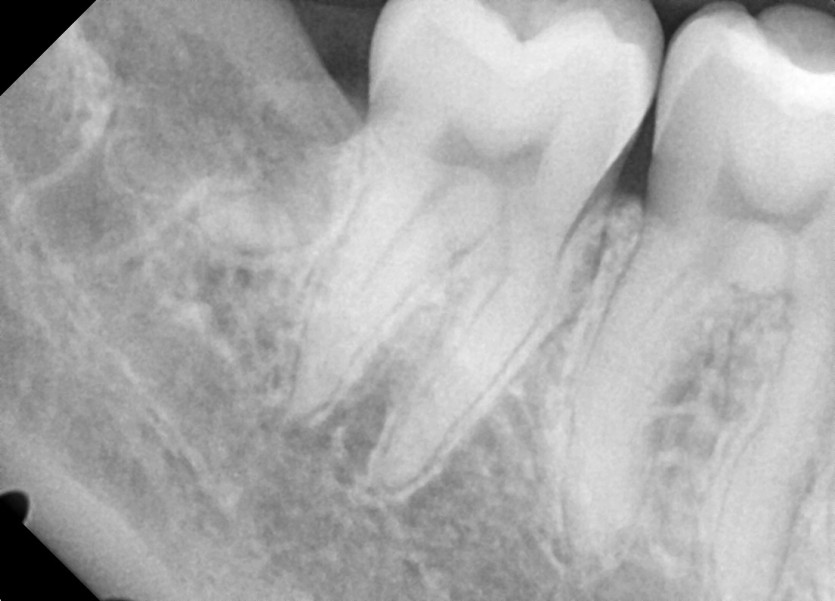

#18,28,48 사랑니 발치

구강 외과 전문의가 당일 발치했습니다.